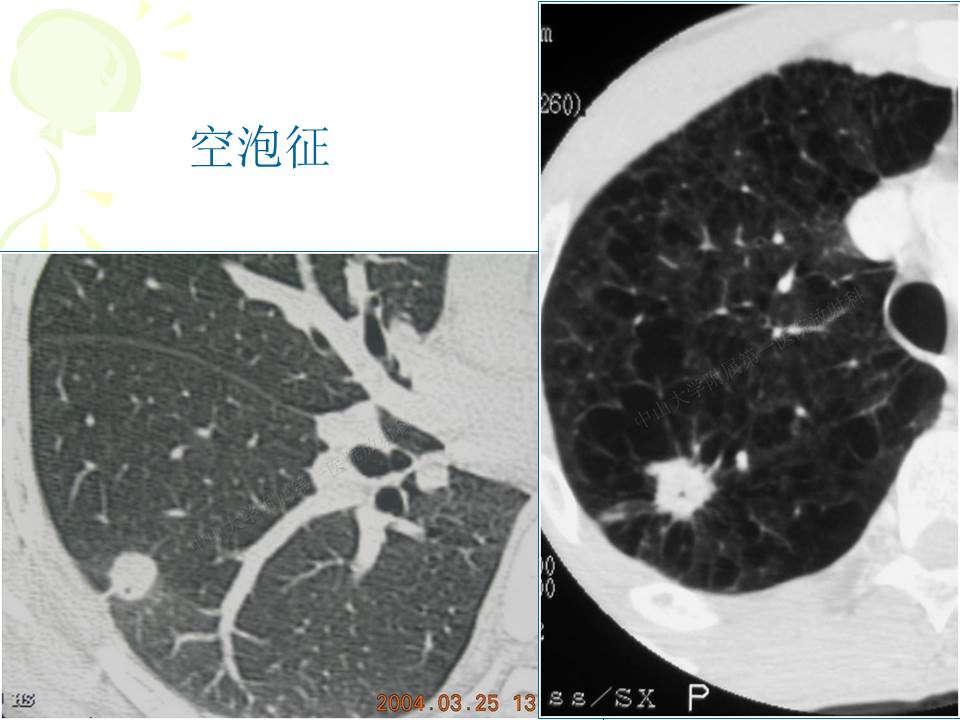

支气管肺癌的影像学诊断